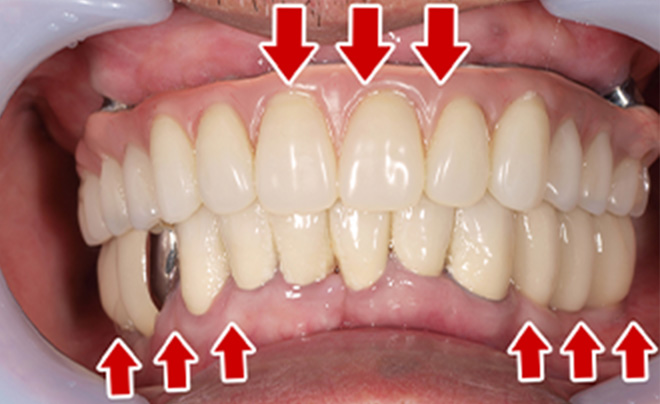

After

| 68歳 男性 | 紹介 |

|---|---|

| 主訴 | れ歯が合わない 食べにくい 人生を豊かにしたい |

| 処置内容 |

上顎4本で12歯(オールオン4)、下顎4本5歯 上下抜歯即時埋入、即時荷重(手術当日にインプラントの上に仮歯装着) |

| 治療費用 | 上顎: 約220万(税込) 下顎: 約180万円(税込) |

| 治療期間 | 上顎: 9ヶ月 下顎: 6ヶ月 |

| リスク |

術後の腫れ、痛み(ピークは3日後、1週間で軽減) 上部構造物、仮歯の破折、人工歯根脱落リスクがあります |